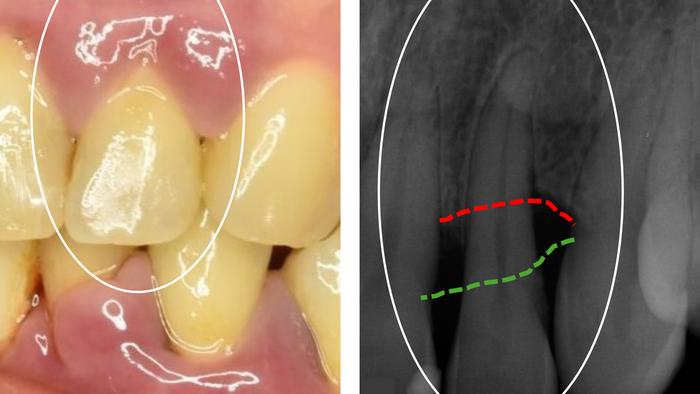

Periodontitis involves inflammation of the gums that leads to the breakdown of the supporting tissues around the teeth and can, in severe cases, result in tooth loss. Individuals with severe periodontitis are also more often affected by other serious diseases, such as cardiovascular disease and rheumatism, but the mechanisms behind these connections remain unclear.